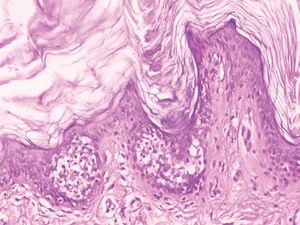

Las exploraciones complementarias realizadas incluyeron una biopsia «en sacabocados» de una zona de piel afectada (figs. 3 y 4) y una analítica general. La analítica general, en la que se incluyeron un hemograma y una bioquímica básica, no mostró alteración alguna.

Fig. 4.--Detalle histológico.

En el examen histopatológico de la muestra cutánea se observó una marcada hiperqueratosis, vacuolización suprabasal y formación de vesículas intraepidérmicas, es decir, un patrón de hiperqueratosis epidermolítica (figs. 3 y 4).

Como se ha comentado antes, para establecer el diagnóstico de un NEE, además de disponer de lesiones cutáneas clínicamente compatibles, es necesario realizar una biopsia cutánea para estudio histopatológico y demostrar en ella la presencia de una hiperqueratosis epidermolítica. Esta última se define como aquel patrón histológico en el que se encuentra una hiperqueratosis compacta, junto con degeneración granular y vacuolar de las capas espinosa y granulosa de la epidermis 7.